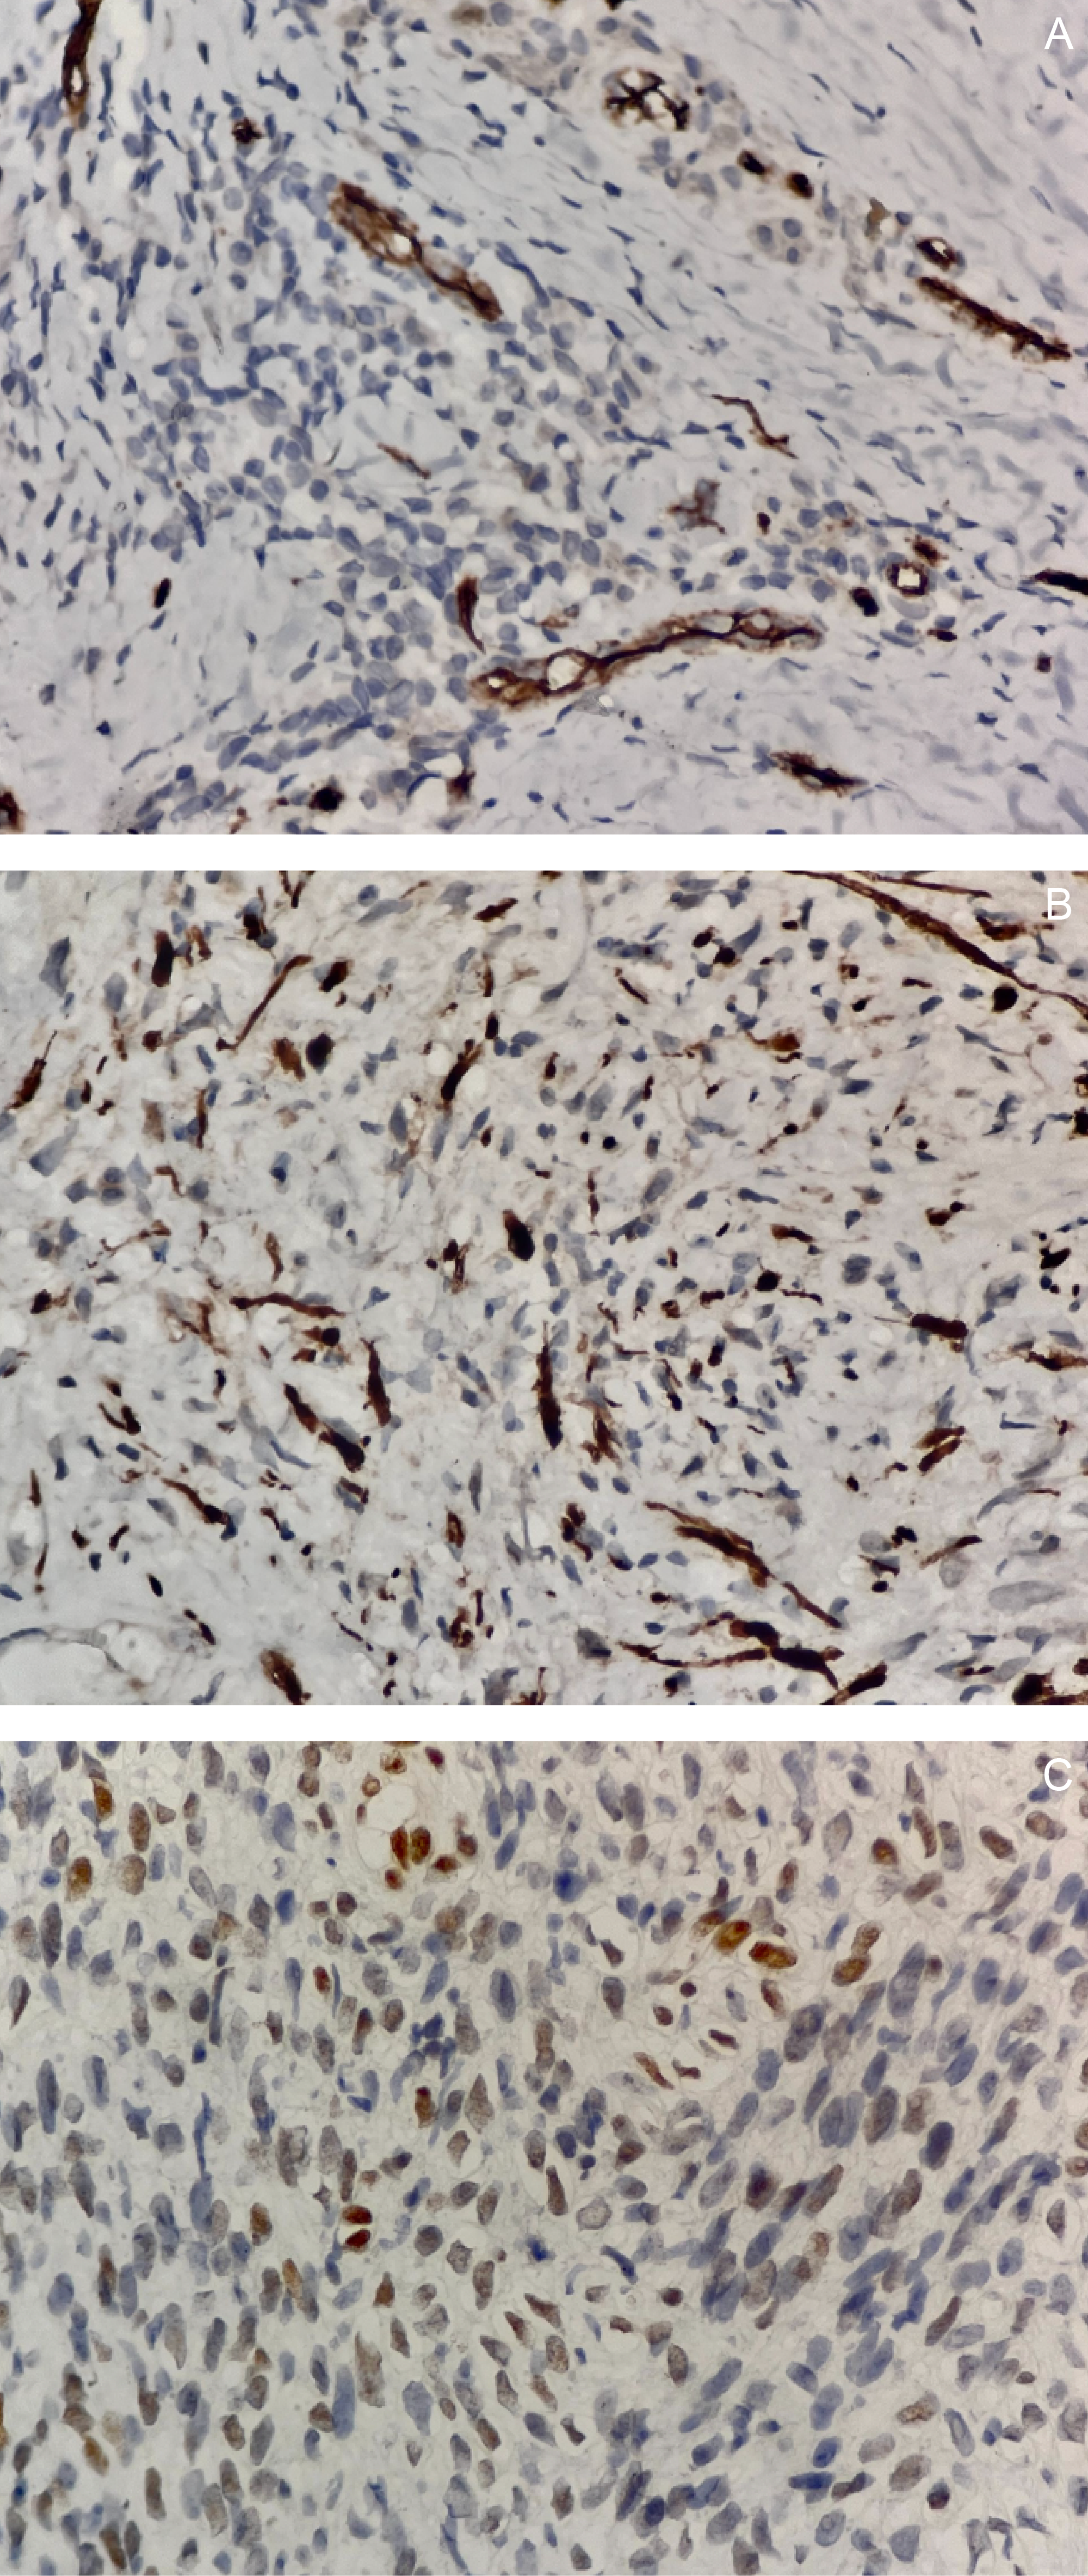

Gross examination of the resected specimen revealed a well-circumscribed mass measuring 16 × 16 × 7.5 cm (Figure 5). Serial sectioning demonstrated approximately 70% necrosis and 40% hemorrhage. Microscopically, the tumor exhibited a marbled low-power appearance with a fascicular growth pattern of atypical spindle cells; all surgical margins were negative for tumor involvement (Figure 6). Additional IHC staining showed focal SOX10 positivity and a mosaic pattern of H3K27me3 expression, indicating partial loss (Figure 7). These histopathologic and immunohistochemical findings were consistent with a low-grade malignant peripheral nerve sheath tumor (MPNST), although the presence of high-grade components in unsampled areas could not be entirely excluded.